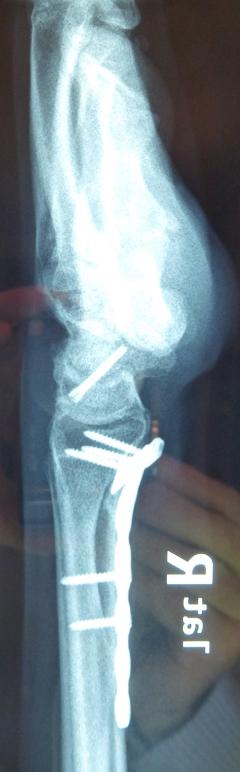

Η αντιμετώπιση της ψευδάρθρωσης του σκαφοειδούς είναι πάντοτε χειρουργική. Με ραχιαία ή παλαμιαία προσπέλαση αποκαθίσταται ο άξονας του σκαφοειδούς και σταθεροποιείται το σκαφοειδές με ειδική βίδα ή βελόνες, με παράλληλη τοποθέτηση οστικών μοσχευμάτων. Μπορεί επιπλέον να γίνει και οστεοτομία κλειστής σφήνας του περιφερικού άκρου της κερκίδος. Στις περιπτώσεις άσηπτης νέκρωσης το μόσχευμα πρέπει να είναι αγγειούμενο – για να προσδώσει αιμάτωση στο νεκρωμένο κεντρικό τμήμα – και λαμβάνεται με μικροχειρουργικές τεχνικές από το περιφερικό τμήμα της κερκίδος ή από άλλα τμήματα του σώματος

Μετεγχειρητικά 1

Περίπτωση 2: Μετεγχειρητικά 2